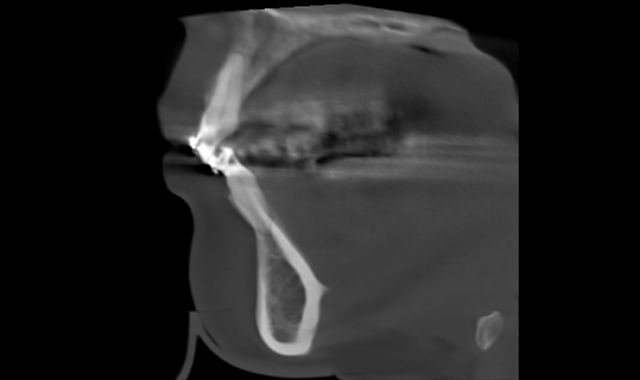

Note in Figure 3 how the roots seem to be violating at the cortical bone of the alveolar housings. The thickness of this slice is 5mm. Figure 4 is the 3D rendering of the same scan. The brackets placed on this patient had a -6 degree torque. Perhaps this patient would have been better served with -1 degree torque. The upper incisors had a 17 degree torque. Perhaps more torque would have kept the roots of the teeth of the upper incisors in the alveolar housing. This is just one simple example of how the specialty must start looking at the anatomy of our patients.

Fig. 3